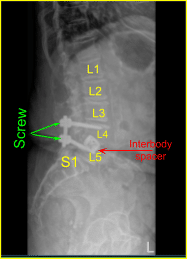

Given the concern for the implant in the prone position and our feeling that the endplates may have fractured more, we exposed the transverse processes for L4 and L5 and used the drill to create pilot holes in the pedicle on the left side at L4 and L5. Under fluoroscopy, we guided probes through the pedicles and tapped each pedicle, then placed pedicle screws into L4 and L5.

These screws were stimulated, and checked under fluoroscopy, and then a rode was placed and cap screws were given a final tightened. On the right side and left side, we decorticated the facets and transverse processes and placed our fusion mass for arthrodesis.